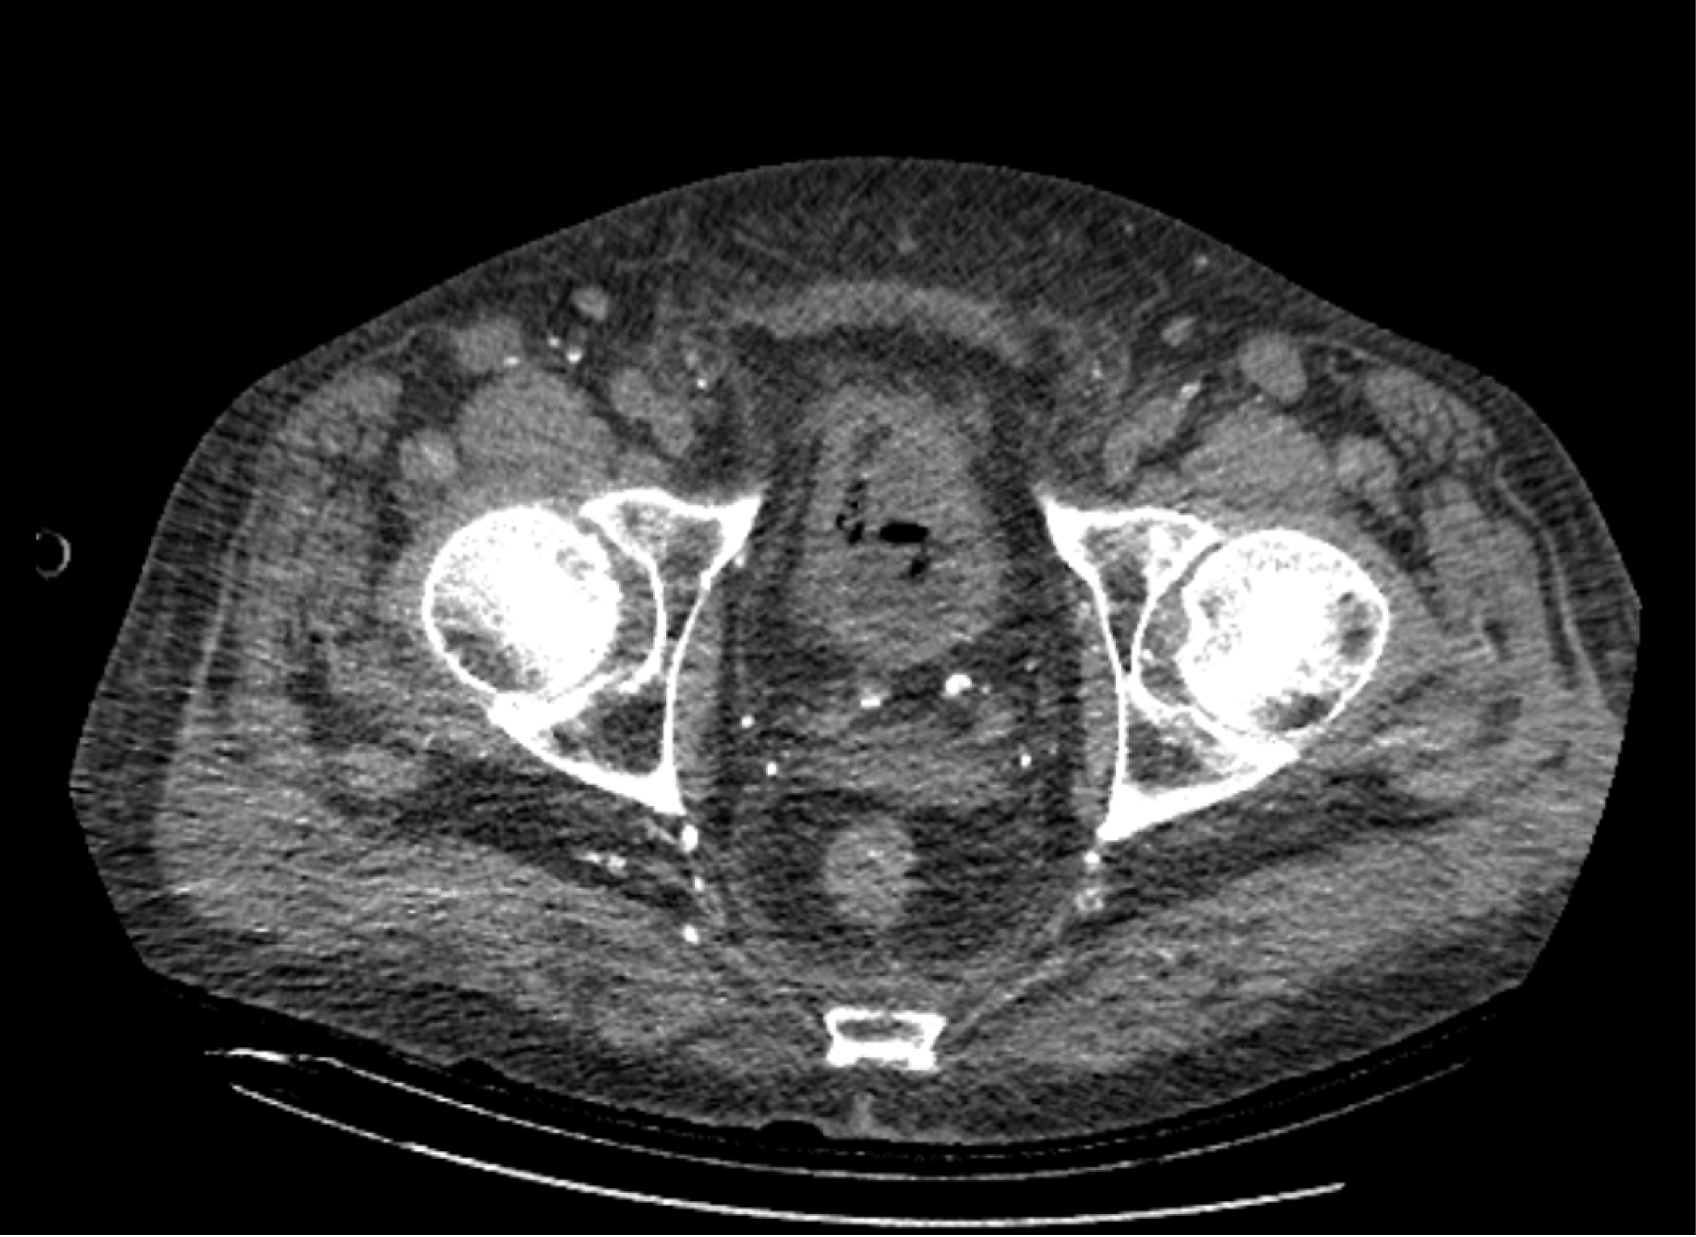

На следующий день состояние пациента оставалось тяжелым, с отрицательной динамикой, креатинин сыворотки возрос до 735,2 ммоль/л, Появились жалобы на слабость, тошноту. При осмотре: живот мягкий, вздут по всем отделам, при пальпации болезненный. Область почек не изменена, при пальпации безболезненна, патологических изменений в области почек не выявлено. Симптом поколачивания отрицательный билатерально. При УЗИ были обнаружены плевральный выпот по 300–400 мл с каждой стороны, гепатомегалия, увеличение размеров селезенки, асцит. Кроме того, в обеих почках были визуализированы тени, характерные для конкрементов. По данным компьютерной томографии (КТ) конкрементов не обнаружено, но в лоханке, на всем протяжении левого мочеточника и, частично, в правом мочеточнике, а также в мочевом пузыре визуализировался газ (рис. 1–6).

Рис. 3. Компьютерная томография органов брюшной полости, забрюшинного пространства, органов малого таза. Газ в левом мочеточнике